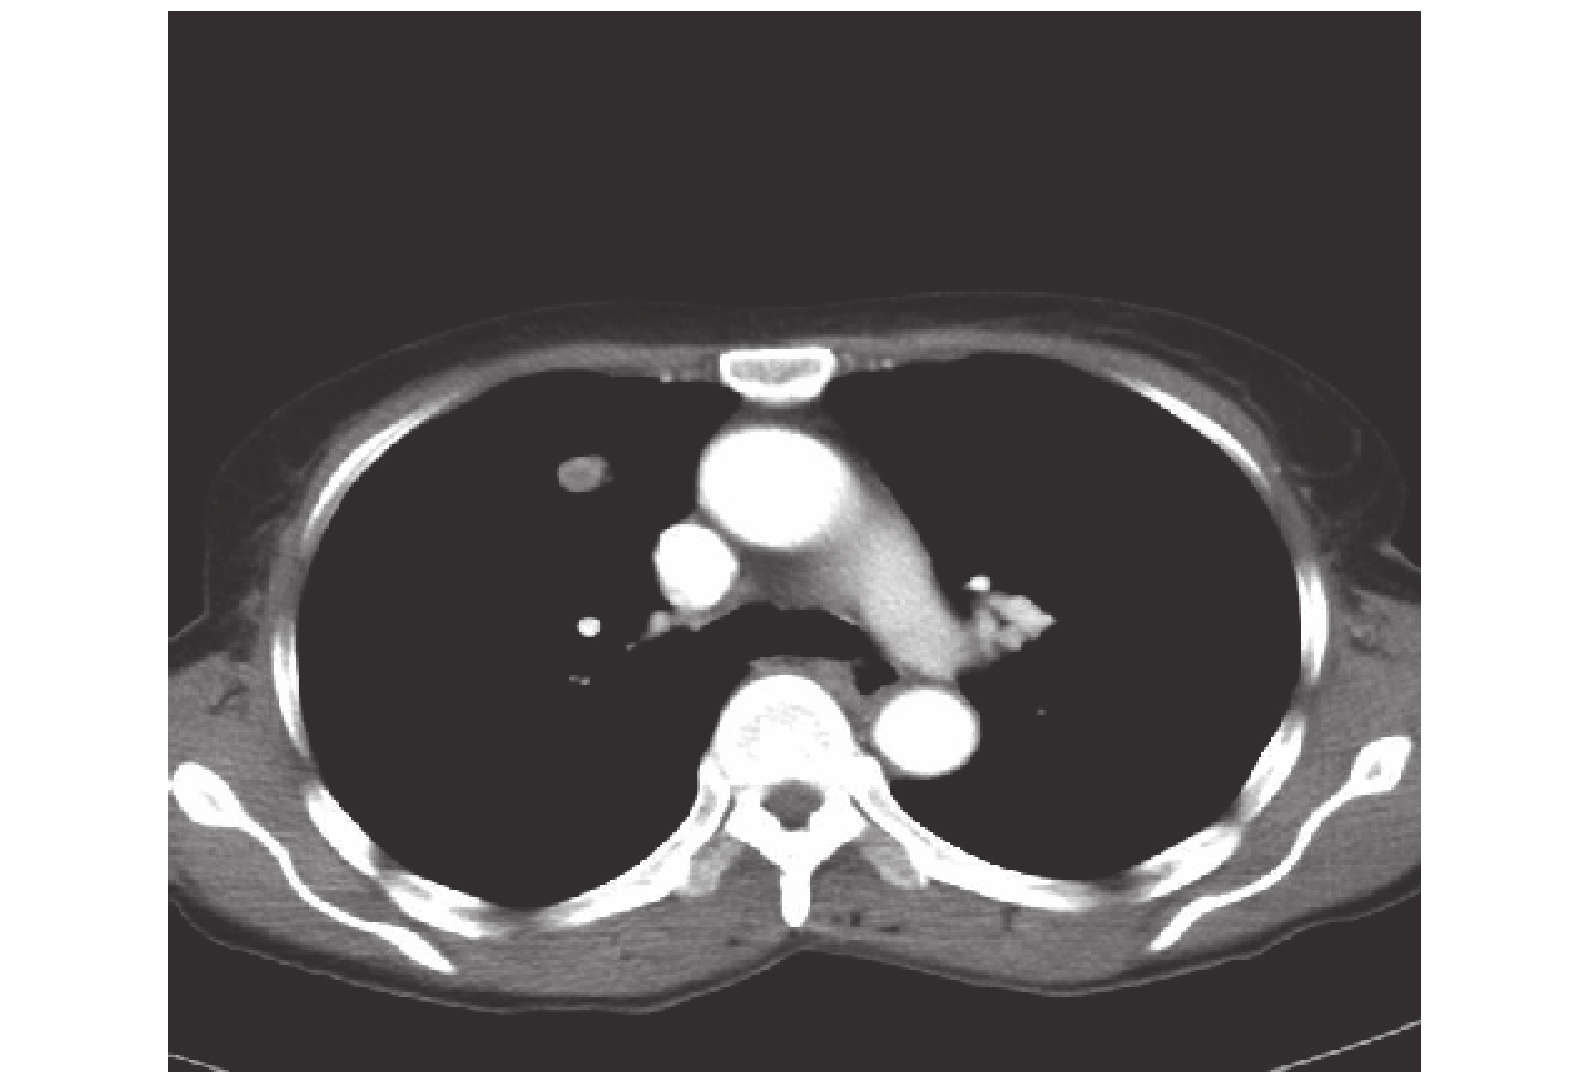

臨床資料 患者,女,60 歲,哈薩克族,既往身體健康,因“進行進咽下困難 4 周”來院就診。胸部 CT 示:右肺上葉前段可見類圓形高密度影,邊緣尚光整,可見淺分葉,所見氣管、支氣管走行通暢(肺窗,圖 1)。右肺上葉前段病灶大小約 12.9 mm×14.3 mm,CT 值 55 Hu;食管中下段管壁不均勻增厚(縱隔窗);胸部諸構成骨未見明顯骨質破壞;增強 CT 示:右肺上葉病灶呈不均勻強化(骨窗,圖 2),動脈期 CT 值 66 Hu,靜脈期 CT 值 76 Hu。食管中下段增厚管壁明顯強化,較厚處約 13 mm(圖 3),縱隔內未見明顯腫大淋巴結影,食管中下段管壁不均勻增厚,結合病史,考慮惡性;右肺上葉前段占位性病變,提示(1)轉移?(2)周圍性肺癌?胃鏡及病理活檢提示:食管中下段鱗癌(圖 4)。頭顱、腹腔、盆腔 CT 檢查及全身骨掃描未見明顯轉移灶,臨床診斷:(1)食管中下段癌(C-T2N0M0ⅠB 期);(2)右肺占位待查。行食管癌根治術(Ivor-Lewis 術式)+右肺上葉楔形切除術,術中觸及右肺上葉大小約 1.5 cm×1.5 cm×1.2 cm,實性結節,質韌,并完整切除。常規清掃胸腹腔淋巴結,術后淋巴結陰性(0/31),食管切緣未見癌組織,肺結節切緣為正常肺組織,肺結節病理大體標本示腫塊大小 1.4 cm×1.3 cm×1.0 cm,切面呈暗紅色,鏡下觀察可見:腫瘤組織與正常肺組織間邊界清,瘤細胞由透亮細胞或胞漿豐富的嗜酸性細胞,細胞多排列成斑片狀,部分圍繞血管分布,細胞核尺寸差異大、未見明顯異型及核分裂像(圖 5),診斷為原發性肺血管周上皮樣細胞瘤(perivascular epithelioid cell neoplasm,PEComa);免疫組織化學結果示雌激素受體(estrogen receptor,ER):陰性(–),孕激素受體(progestrone receptor,PR)陰性(–),CK/L:上皮陽性(+),癌胚抗原(carcino-embryonic antigen,CEA):陰性(–),Vim 陽性(+++),S-100:弱陽性(±),人黑色素 45(human melanoma black 45,HMB45)陽性(++),符合肺透明細胞瘤(clear cell tumor,CCT),屬于血管周上皮樣細胞瘤家族。術后恢復良好,1 周后出院。兩年 2 個月后患者來院復查,無明顯不適;胸部 CT 提示食管癌術后,吻合口未見明顯異常;右肺上葉高密度影,右肺門及縱隔新發腫大淋巴結,考慮肺 PEComa 復發及轉移可能(圖 6);胃鏡取吻合口周圍組織活檢未見食管癌復發,腹盆部及頭顱 CT 未見明顯異常。患者拒絕進一步診治出院。

原發性肺 PEComa 影像學上常表現為類圓形軟組織影,邊緣較光滑,本例患者可見淺分葉,可強化,也有文獻報道病灶規整,無分葉和強化者,需與肺部炎性假瘤、錯構瘤等鑒別。本例患者同時合并食管癌,應考慮食管癌肺轉移可能。由于原發性肺 PEComa 極其罕見,可統計分析病例數極少,暫無法根據目前的文獻報道總結出此類疾病的特異臨床癥狀、體征和影像學特點,本例患者亦無特異性表現。明確診斷只能依靠病理學和免疫組織化學,顯微鏡下肺 PEComa 常由巢狀、腺泡狀或斑片狀排列的透明細胞組成,部分圍繞血管分布或者呈血管周放射狀排列,瘤細胞巢之間可有豐富、纖細的血管網;瘤細胞呈圓形或多邊形,胞質豐富透亮、嗜酸性;血管壁或腫瘤間質可發生玻璃樣變性[16-17]。免疫組織化學顯示腫瘤細胞特征性表達黑色素瘤抗體 HMB-45、肌源性抗體平滑肌抗體(smooth muscle antibody,SMA),腫瘤細胞波形蛋白(vimentin)陽性表達;肌漿蛋白(myogenic)、S-100 少部分陽性表達[13];嗜鉻粒蛋白(chromogranin)、突觸泡蛋白(synaptophysin)一般不表達。病理方面需與肺原發透明細胞癌、腎臟轉移的透明細胞癌、轉移性黑色素瘤及女性肺部子宮內膜異位相鑒別;本例患者病理活檢結果提示 CCT,或稱糖瘤(sugar tumor),同時合并食管癌,極易誤診;鑒別診斷主要依靠免疫組織化學染色法。原發性肺 PEComa 報道極少可能與漏診和誤診有關,該病的確診對病理科的設施、醫師的經驗及知識面要求均較高,對于 PEComa 患者,須行全身檢查,此類疾病可同時原發于多個部位,而且肺是肺外 PEComa 最常轉移部位[18]。